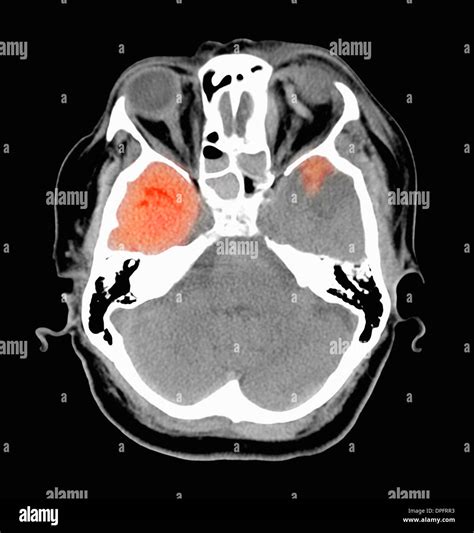

• Differentiating subdural hemorrhage from other types of intracranial bleeding, such as epidural or intraparenchymal hemorrhages.

• Acute Subdural Hemorrhage: Occurs within 72 hours of the injury and appears as a hyperdense collection on CT images.

CT scans use X-rays to create cross-sectional images of the body. In the case of subdural hemorrhage, the CT scan focuses on the brain to detect any abnormalities. The images produced are highly detailed and can show the exact location and size of the hemorrhage. This information is essential for planning surgical interventions if necessary.